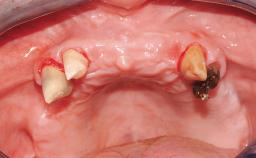

Immediate Loading of Six Implants in the Maxilla and Final Restoration with a Full-Arch CAD/CAM Zirconia FDP

A 63-year-old male patient was referred for a consultation and treatment of partial edentulism in the maxilla. The patient presented with residual anterior teeth and declined a partial removable prosthesis. He reported that the maxillary posterior teeth had been extracted due to mobility and periodontal disease two months before the consultation. The patient’s chief complaint was that his residual maxillary teeth were mobile and that he was unable to chew. The patient’s desire was a stable and comfortable fixed maxillary rehabilitation. The patient was a light smoker (fewer than 10 cigarettes/ day), and his medical history was without significant findings. He was not on any regular medication at the time of consultation. The extraoral examination revealed a normal physiognomy with a correct distribution of the facial thirds. The patient presented a low lip line, and the transition line between teeth and soft tissues was not exposed during a forced smile.

Soft Tissue Anatomy Intact Defective

Bone Volume Horizontally and vertically sufficient Horizontally deficient Deficient vertically or deficient vertically AND horizontally

Periodontal Status History of periodontitis or genetic predisposition